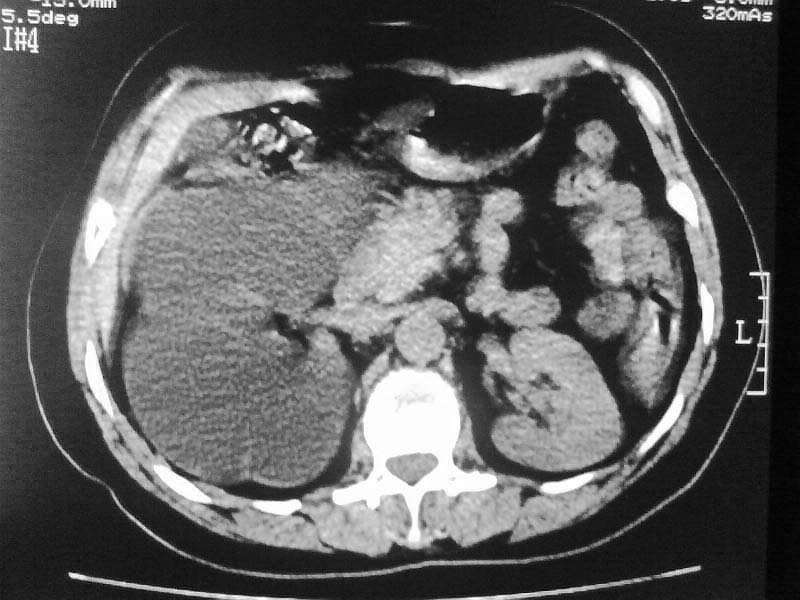

标题: CT20044:女,45岁,腰痛2年,双肾结石,右输尿管结石,右肾重度积 [打印本页]

标题: CT20044:女,45岁,腰痛2年,双肾结石,右输尿管结石,右肾重度积

支持双肾结石、右输尿管上端结石,右肾重度积水

右肾梗阻性积水。

支持 右肾结石、右输尿管上端结石,右肾重度积水。

双肾结石、双输尿管结石并右肾积水。